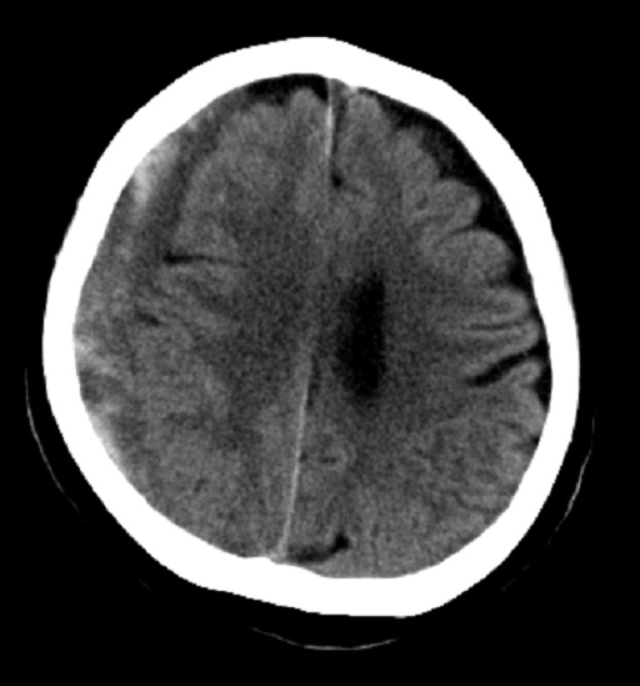

- 硬膜下血腫